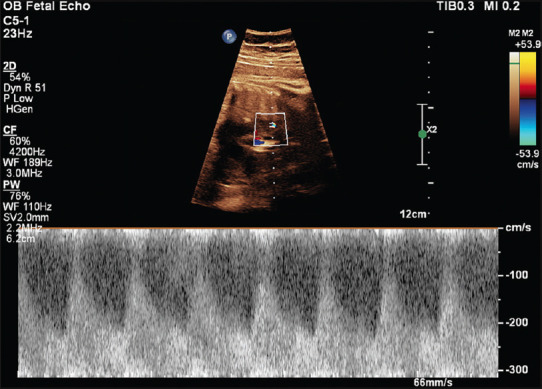

Fetal ductal constriction: An ominous but treatable entity!

胎儿导管收缩:一个不祥但可治疗的实体!